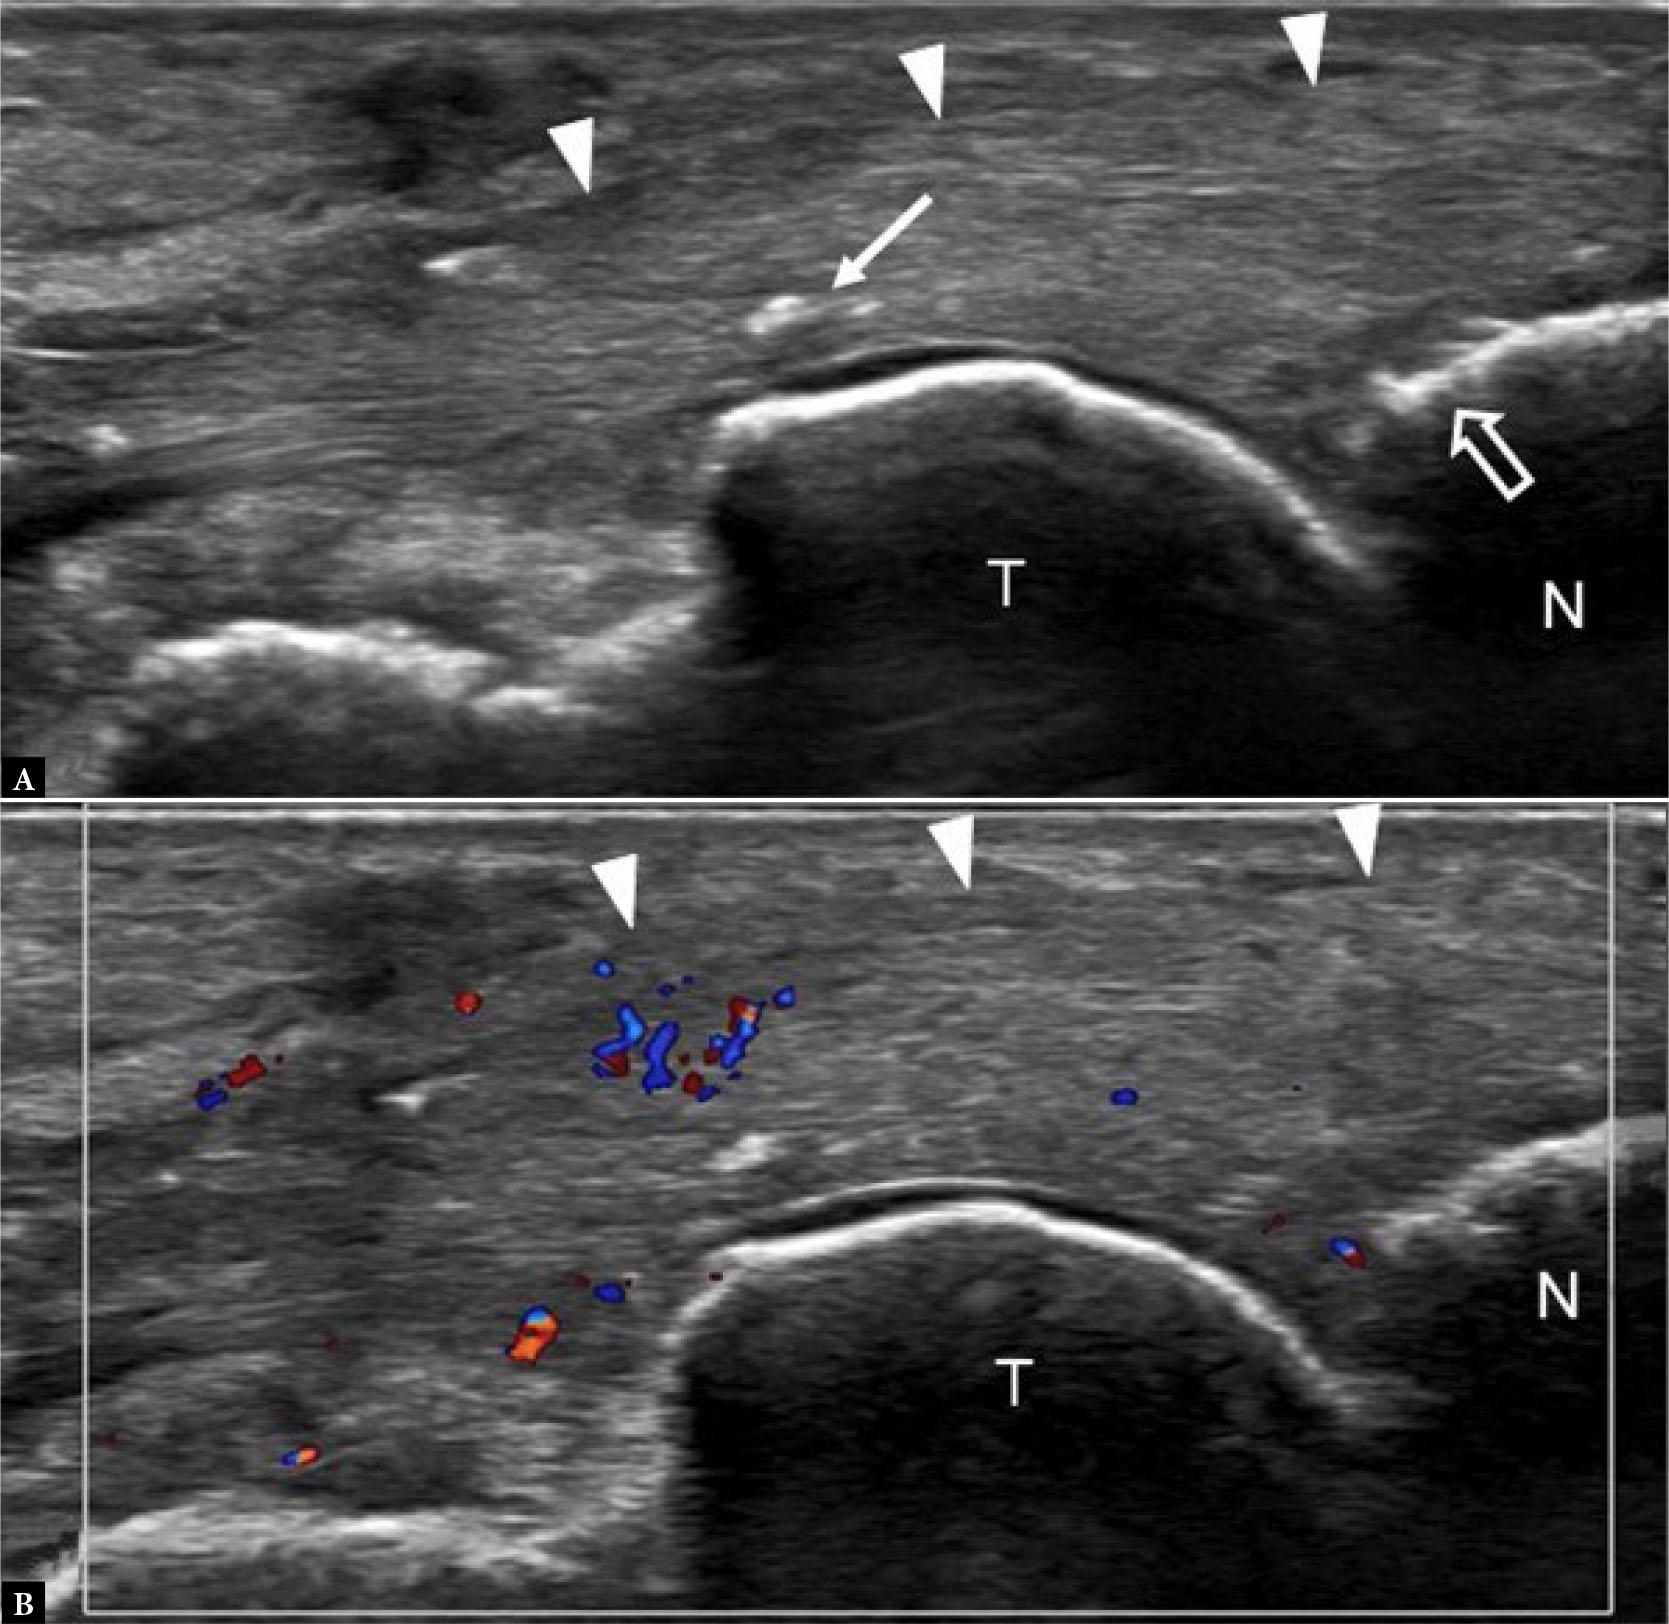

Stress fractures typically occur in young to middle-aged individuals undertaking unaccustomed high levels of exercise over an extended period. The 2nd and, less frequently, the 3rd metatarsal mid-shafts are commonly affected sites(1) (Fig. 1). The base of the 2nd metatarsal is splinted between the distal end of the medial cuneiform and the 3rd metatarsal bone. It is also a key weight-bearing bone, making it more susceptible to injury. The 1st, 2nd and 5th metatarsal bases, the navicular, cuneiform, cuboid, and medial sesamoid bones are additional common sites of stress fractures in the mid- and forefoot(1,2) (Fig. 2). Radiographs are normal in the earliest stages of stress fracture. US at this juncture may reveal a cuff of echogenic thickening due to thickened periosteum (‘periostitis’) around the cortex of the affected bone area. The cortex may be less distinct than usual, together with juxtacortical soft tissue edema and hyperemia (Fig. 1). While such findings are non-specific, they are usually diagnostic in the appropriate clinical setting without the need for additional imaging other than radiographic follow-up. MRI will provide even earlier detection of stress fracture than US, revealing focal bone marrow edema (BME) at the affected site, often with a thin hypointense fracture line(1) (Fig. 2). In the appropriate clinical setting, BME on fat-suppressed, fluid-sensitive sequences without a visible fracture line is termed a ‘stress reaction’ rather than a ‘stress fracture’(1). Radiographs and US will typically be normal in stress reaction. It is important to correlate any BME with clinical symptoms, as BME may occur due to physiological bone remodeling without necessarily being reflective of an injurious stress reaction(3).

Fig. 1.

41-year-old female with forefoot pain and swelling for one month. There was no specific traumatic event and no undue sporting activity. A tendon injury was suspected clinically A. Dorsoplantar (DP) radiograph shows normal 2nd metatarsal bone (arrowhead). B. Longitudinal greyscale and C. color Doppler, and D. transverse greyscale US images show moderate severity localized periosteal thickening (open arrow) of the 2nd metatarsal shaft dorsally, with moderate adjacent soft tissue thickening (open arrowhead) consistent with active stress fracture. E. Radiograph three months later showed marked periosteal thickening of the 2nd metatarsal shaft (arrow) compatible with healed stress fracture